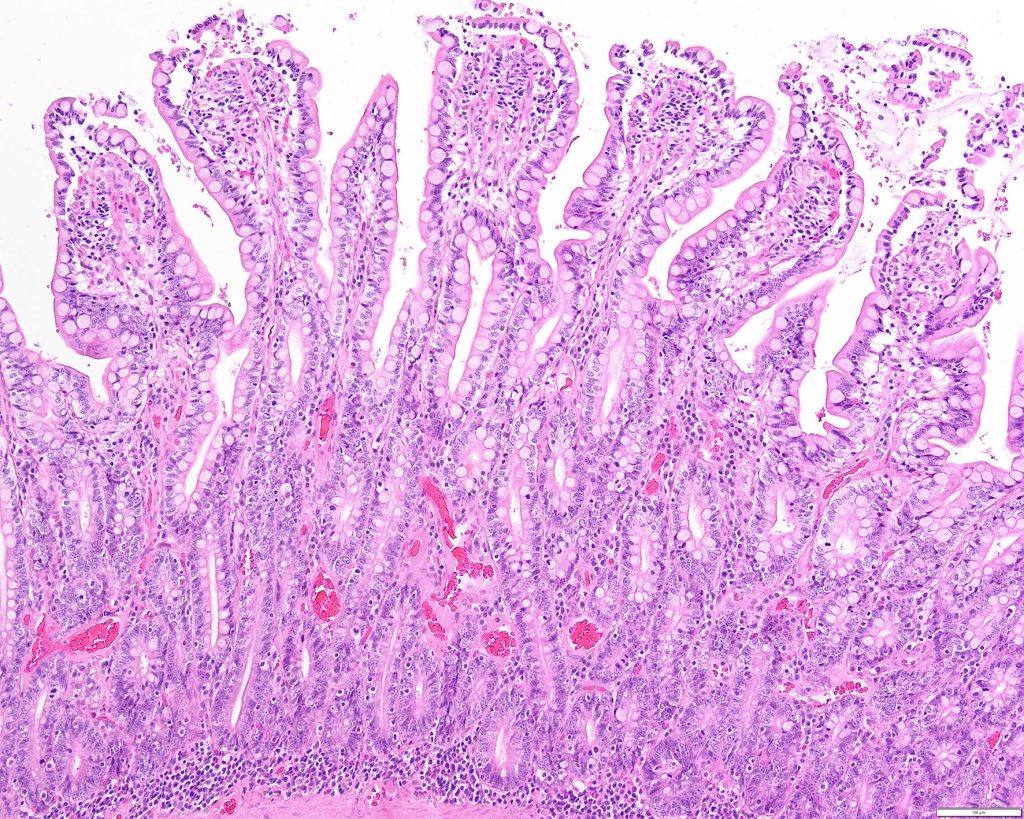

Normaal gesproken worden darmcellen in de crypten van Lieberkühn aangemaakt, vervolgens naar de villi (“vingers” van de darmwand) getransporteerd en binnen een aantal dagen in de darm afgescheiden, waarbij ze continu aangevuld worden vanuit de crypte. De cellen schuiven hierbij op vanuit de cryptes naar de villi. Dit is een normaal proces en duurt enkele dagen. Bij de meeste darmvirussen worden de villi aangetast. Dit is vervelend, maar doordat de nieuwe cellen continu via de crypten worden aangevuld, duurt de diarree hooguit een paar dagen. Het parvovirus tast echter de crypten aan. Hierdoor worden er geen nieuwe darmcellen aangemaakt, waardoor in het normale proces van afscheiden van de villi-cellen, er ineens geen fatsoenlijke darmwand meer is. Er is nu een poreuze verbinding met het lichaam en bacteriën kunnen vanuit de darm het lichaam binnendringen. De virusdeeltjes hebben een voorkeur voor snel delende cellen, waardoor het beenmerg en de lymfeknopen ook aangetast worden. De hond wordt vervolgens ernstig ziek.